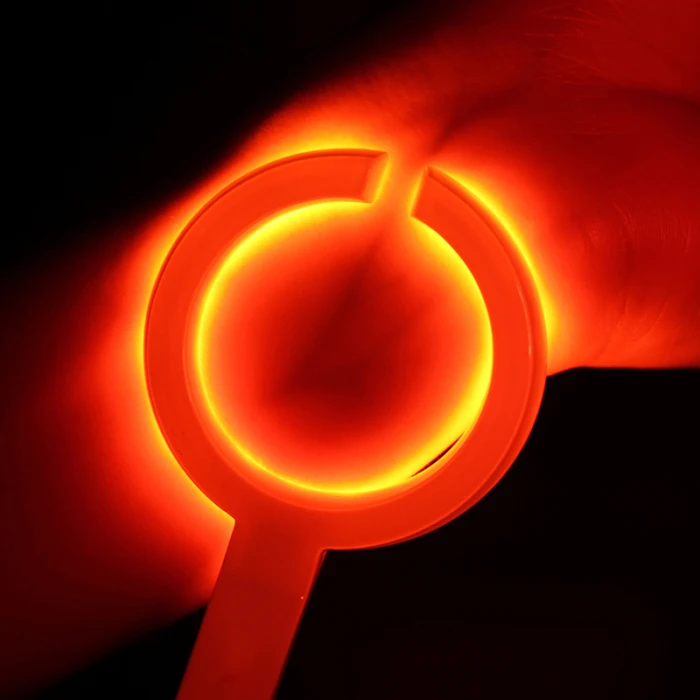

Взрослая детская визуализация инфракрасный васкулярный IV вены Finder Transilluminator вены просмотра TN88

Наше портативное устройство для просмотра Вены-Доступный портативный обнаружитель вен для общего доступа вены у взрослых и детей.

Питание от зарядного устройства непосредственно при использовании с 15 светодиодами, управляемыми одним переключателем.

Он используется для эффективного доступа IV в аварийной медицине.

Материал: АБС-пластик

Цвет: белый

Размер: 90 мм x 47 мм (длина ручки x Диаметр)